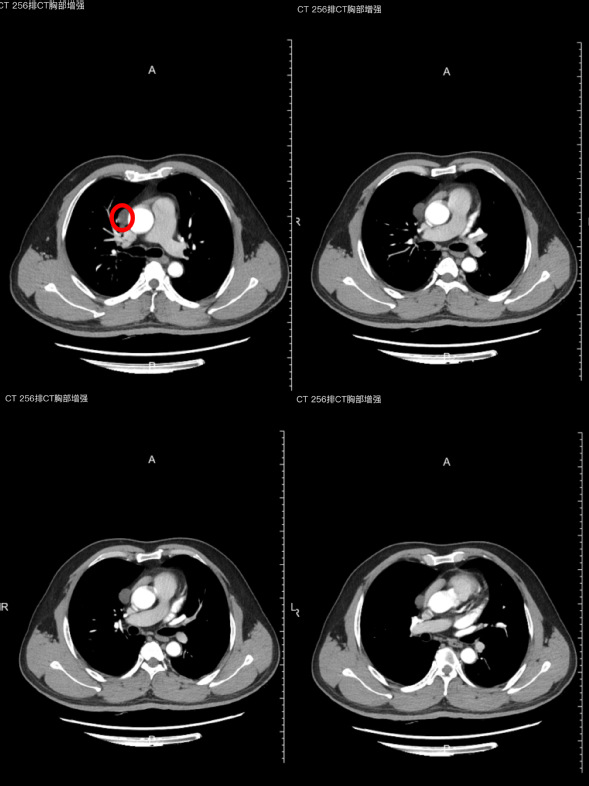

近日,44岁兰先生(化名)因胸痛完善胸部CT后,在中纵隔心包旁发现一个直径3.0厘米左右的肿物。因肿物与心脏大血管及肺静脉关系密切,风险较大,患者想要在更安全、更少的痛苦的条件下完成手术切除肿物,得知我院胸心外二科开展了无管化胸腔镜纵隔肿物切除术后慕名而来。

我院胸心外二科主任任海与患者及家属沟通病情及诉求后,给予患者办理入院手续。患者入院后仅1日,就完善了所有的术前检查。术前,任海主任根据患者胸部增强CT制定详细的手术计划,并与麻醉科进行了充分的讨论及制定了详细的术前准备。术中,麻醉师马琳主治医师根据患者情况给予患者喉罩全身麻醉,手术过程中发现纵隔肿物与上腔静脉粘连紧密,而患者采用单孔胸腔镜手术术中黏连大大增加了手术难度,一旦损伤大血管将会有致命的风险,经过任海主任的仔细小心的剥离肿物及上静脉的粘连,保护心包及上腔静脉,顺利完整的将纵隔肿物切除,术中出血不到5毫升。而手术切口仅仅不到4厘米。患者术前无需放置导尿管,术后无需要留置胸腔引流管。手术结束后兰先生恢复自主呼吸,不久苏醒,给予拔出喉罩,可以坐起与医生对话,安全返回病房。术后3天无明显不适,出院回家,手术切口无需拆线。